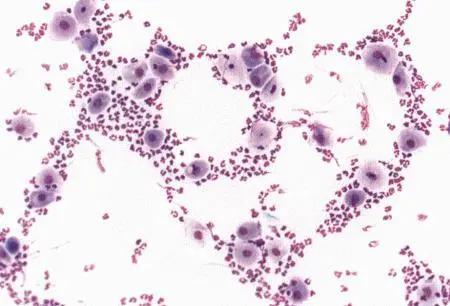

Рассматриваются следующие вопросы: нормальная физиология собак и кошек; болезни репродуктивной системы; бесплодие самок и бесплодие самцов; нормальное функционирование и дисфункция молочных желез; спаривание; искусственное осеменение; протекание беременности и роды; уход за новорожденными щенками и котятами, их наследственные и инфекционные болезни; техника оперативных вмешательств на репродуктивных органах; фармакологический контроль репродукции.